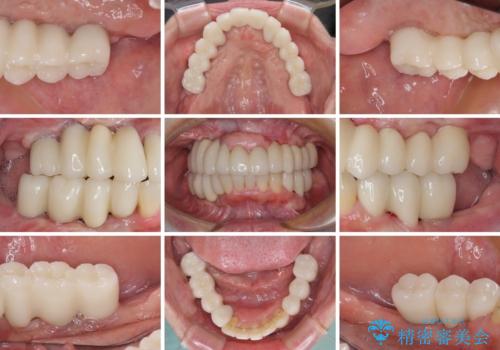

- 歯周病を放置したことで奥歯が抜け、前歯も痛くなってきたとのことで来院された患者様です。

奥歯はほとんどを抜歯しなければならない状態であり、抜歯をせずに済む歯も歯周外科処置や矯正治療を行う必要がある状態でした。

歯を抜かないといけない部分はインプラントとオールセラミッククラウンにより咬合を回復させ、歯周外科処置を行う歯については、同じくオールセラミッククラウンにて補綴治療を行うこととしました。

外科処置を多く行ったため、その待ち時間が長くかかり、さらには途中矯正治療も行なったので、治療期間は長期間となりました。